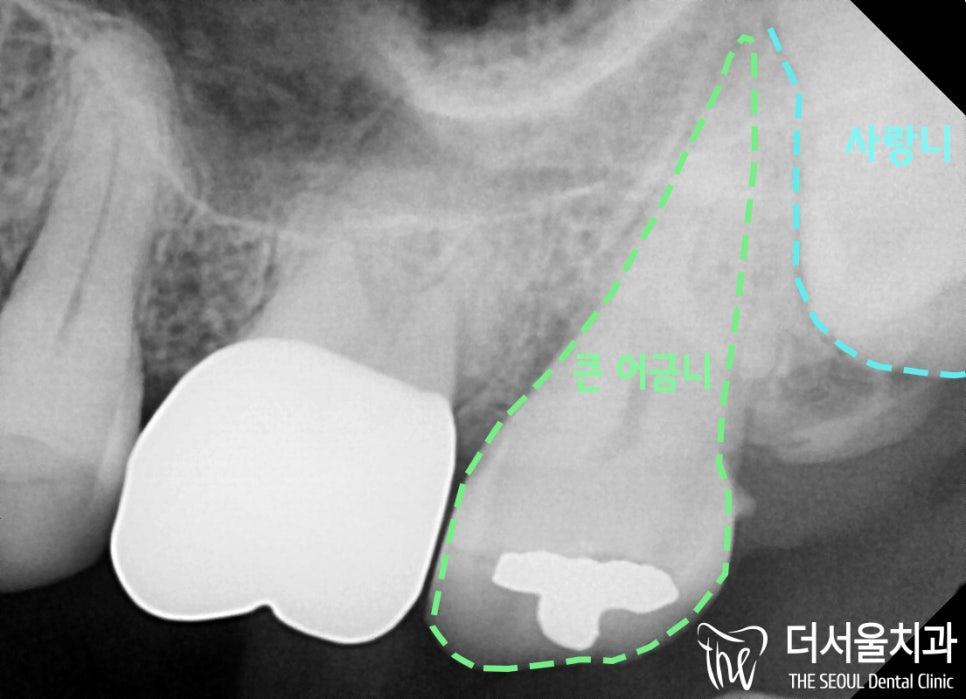

안녕하세요. 박현준 원장입니다. 제가 3년전에 적었던 글을 하나 보여드릴게요. (최근에 치료가 끝났거든요!) 이전 글의 내용을 정리하면 순서로 설명을 드렸었습니다.